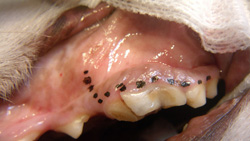

Step 12

Once all roots are removed (clinically and radiographically), each root alveolus is curetted and flushed with sterile saline and any bony protuberances are smoothed with a round, football-shaped, or tapered bur.

Step 13

The mucoperiosteal flap is now ready for closure over the extraction site (A). Note the triangular flap and triangular defect (B). If additional laxity in the gingival flap is needed for a tension-free closure, the underlayer of the flap (periosteum) can be incised with a scalpel blade or scissors.

A

Step 14

The site is radiographed postoperatively (A) and the mucoperiosteal flap is closed using absorbable suture in a simple interrupted pattern (B).